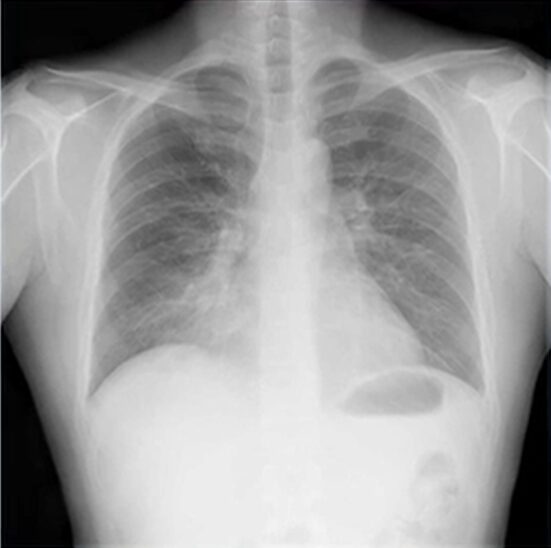

肺炎のレントゲン(X-p)写真

肺炎になってしまっている場合、レントゲン(X-p)には特徴的な所見が映ることが多いです。

どのような所見が映ることが多いか、共有しておきます。

白い浸潤影:

肺炎では、正常な「肺が黒く見える」部分に、炎症が起きている「肺胞に体液が溜まった箇所」が「白っぽく」写ります。

境界が不明瞭:

肺炎の浸潤影は、はっきりと区別できるようなはっきりした形ではなく、境界がぼやけて不明瞭な白い影として現れることが多いです。

肺胞性陰影:

肺胞が炎症を起こし、液体や細胞が溜まることで生じる、比較的はっきりした白い影がみられます。

本症例では、右下肺野に第2級とシルエットサイン陽性(境界不明瞭)の浸潤影を認め、肺の用量に変化がない(変化があったら無気肺考える)ことから肺炎が疑われます。

ちなみに辺縁が外向きに凸なら腫瘤を考えます。